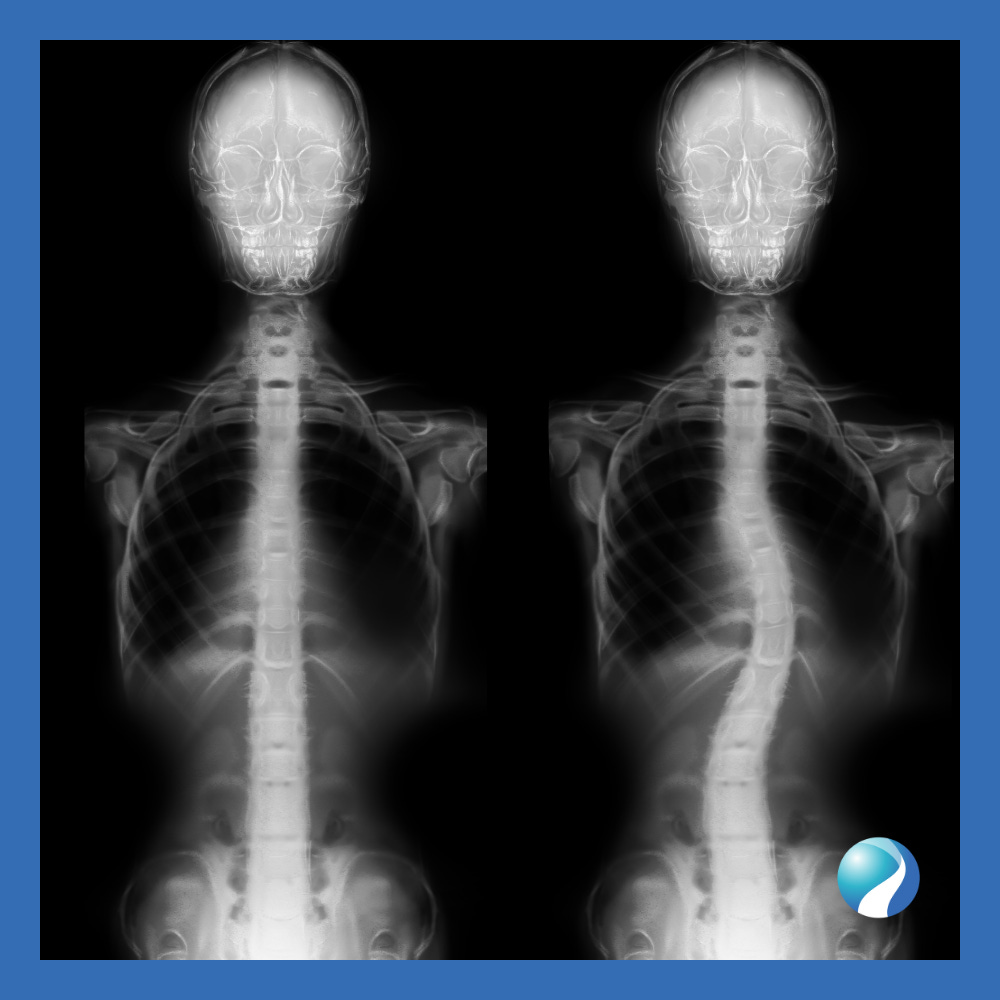

How Is Scoliosis Diagnosed?

Initial screening often involves the Adams Forward Bend Test, where a child bends forward while a healthcare provider observes the spine. If a curve is suspected, X-rays are ordered to determine the degree and type of curvature. Spinal curves are measured using the Cobb angle, a tool that helps determine the severity and appropriate treatment.